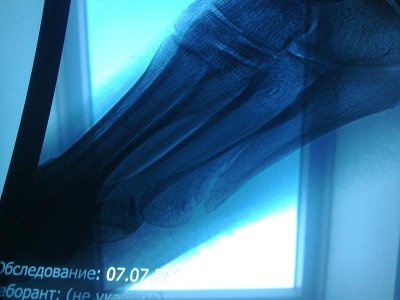

вчера (15июля) делали повторный рентген. состояние стабильное. ренгенолог сказала,что начала образовываться костная мозоль.